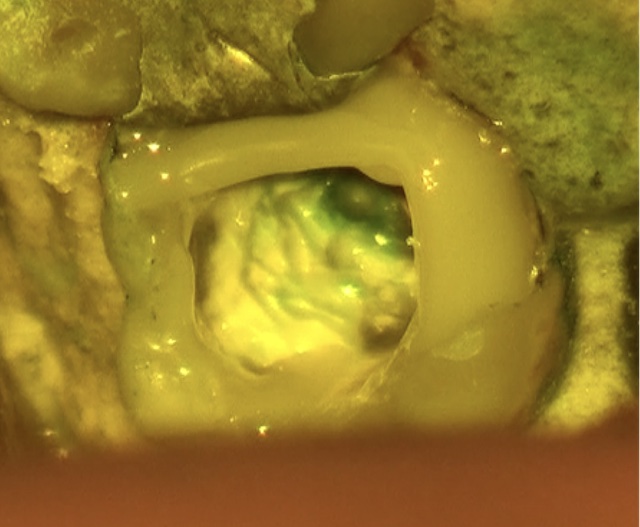

虫歯を除去後、神経が露出しないように丁寧に削合しました。